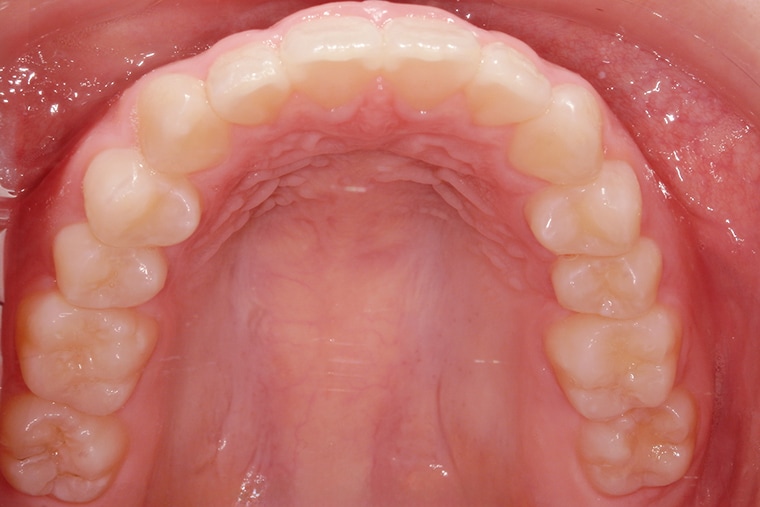

AFTER